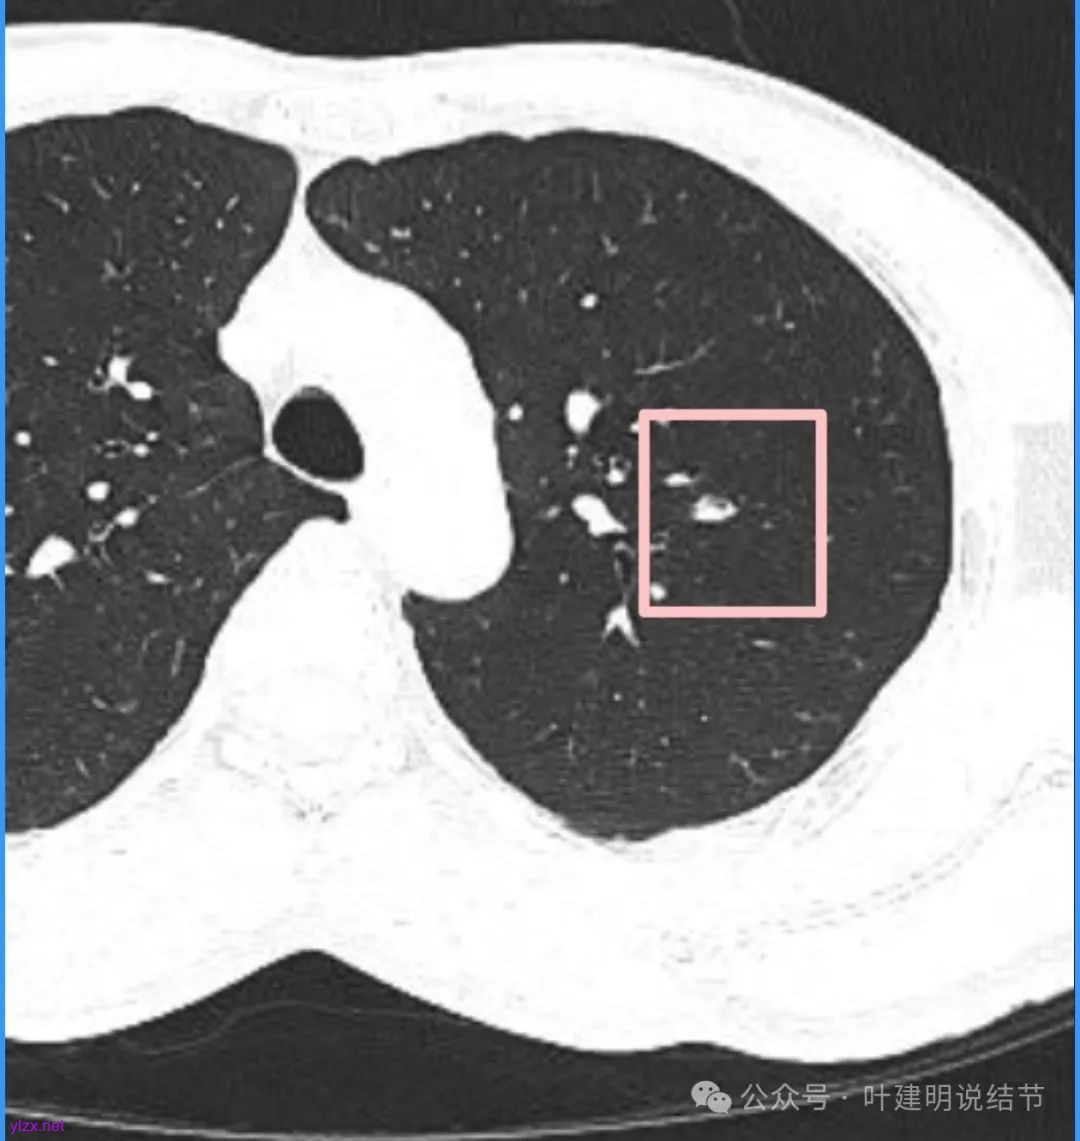

再看看近半年前2024年11月时的影像:

我们发现一是病灶与25年3月的几乎没有区别,二是原来蓝色箭头处不太像血管,而是结节边缘的一部分,而结节灶内又是有扩张支气管的。

左肺上叶这个病灶总体上来讲2025年3月的与2024年11月份相比没有显著进展。我们逐层从细节上去分析,会发现:1、病灶开始出现的层面就有临近的支气管扭曲变形,这些人用肿瘤导致的牵拉不能解释,反而用细支气管扩张伴慢性炎容易解释;2、病灶内部仍然多个层面都有见到扩张的细支气管,可是如果是肿瘤,与导致细支气管扩张相应的病灶本身的收缩力或者边缘毛刺又不明显;3、病灶边缘基本上都比较光滑平直,没有像外周浸润性生长的枫叶或者毛刺;4、虽然有血管贴边或者进入,但是说不上显著的血管异常增粗;5、整体来讲病灶实性成分密度过高,随访对比进展不明显,用结节是恶性不太能够解释相应的影像表现,所以我倾向于考虑是细支气管扩张伴有周围慢性炎或者肉芽肿性炎。至少从风险高低的角度来看,几个月的间隔没有明显进展的情况下加上位置又不好,如果手术需要切除范围比较多,所以应该在随访观察比较稳妥,可以考虑半年复查对比。意见供参考!